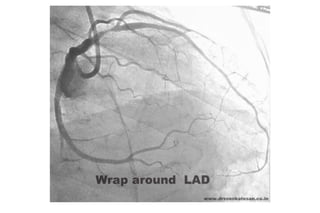

• Wraparound LAD STE INF

Wraparound LAD

STE INF + V4-V5

STD reciproco aVl

ADA larga ocluida distal

ANTERIOR MID-LAD • Distal a Dg1 y S1 D1 • STE V2-V4 S1 • STE máximo en V2 y V3 • No STD en DIII – SENS 41%, ESP 95% • Wraparound LAD STE INF – offset cambios en espejo: STD

Wraparound LAD STE INF + V4-V5 STD reciproco aVl ADA larga ocluida distal

• #76 AD is  graded into three types according to Type 1  :  Falls short  of Apex Type 2 :    Reach up to the LV apex Type 3 : Wraps around LV apex and travels some distance in the posterior Inter-ventricular groove.